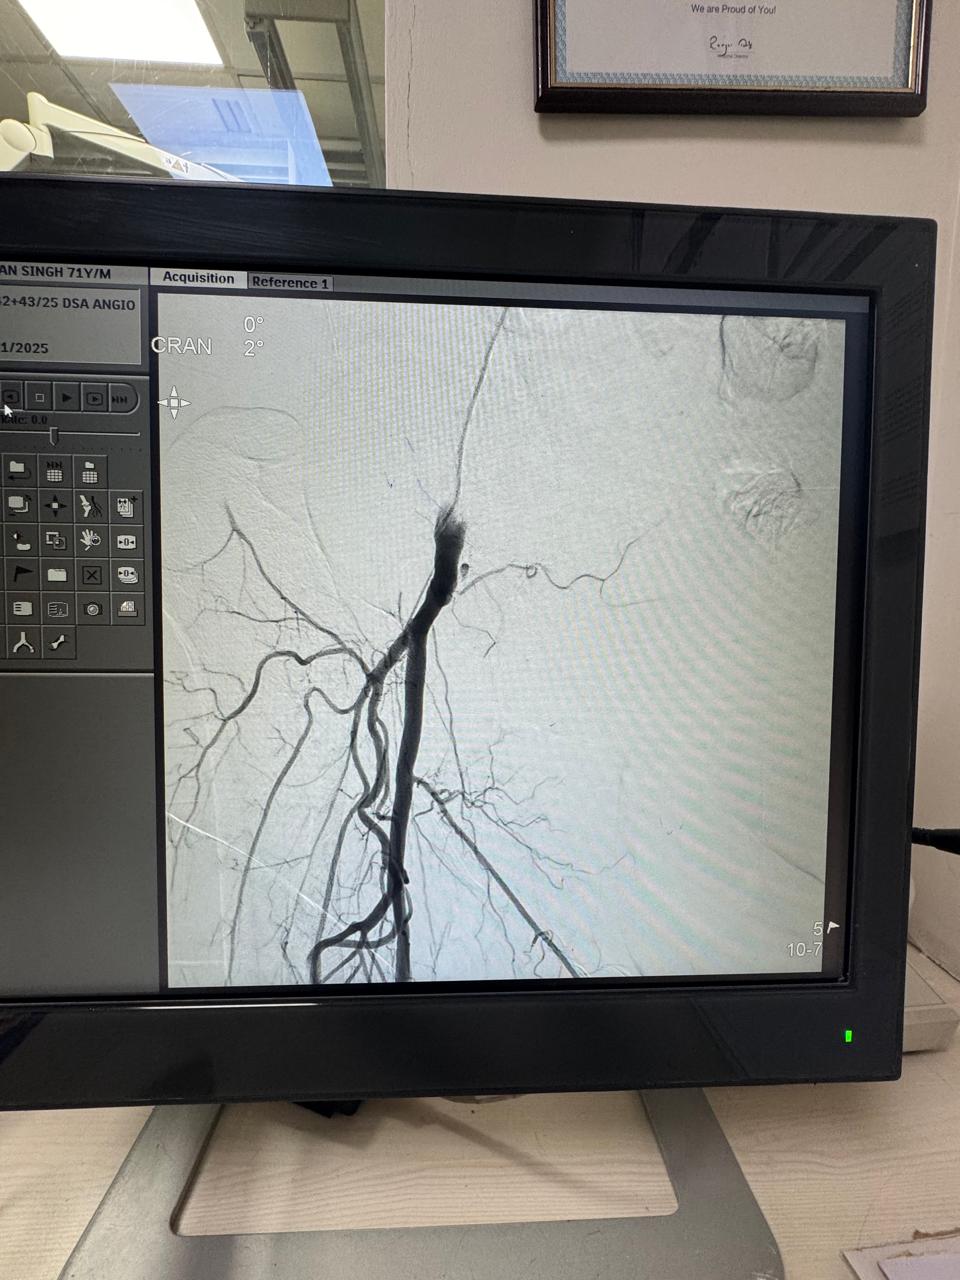

60 year male patient with uncontroll diabetes , forefoot gangrene and below knee vessel disease,below knee angioplasty and debridement done ,also regular dressing and diabetes uncontrol,wound ready to skin graft

Right leg critical ischemia grade 5 Hybrid treatment ( right iliac steering + angioplasty then femoro_popliteal bypass) done. Post -op ATA & PTA palpable confirmed on hand Doppler. Patient all symptoms subsides and walk normally.